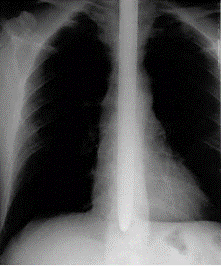

Рентгенография легких, норма

Рак легких